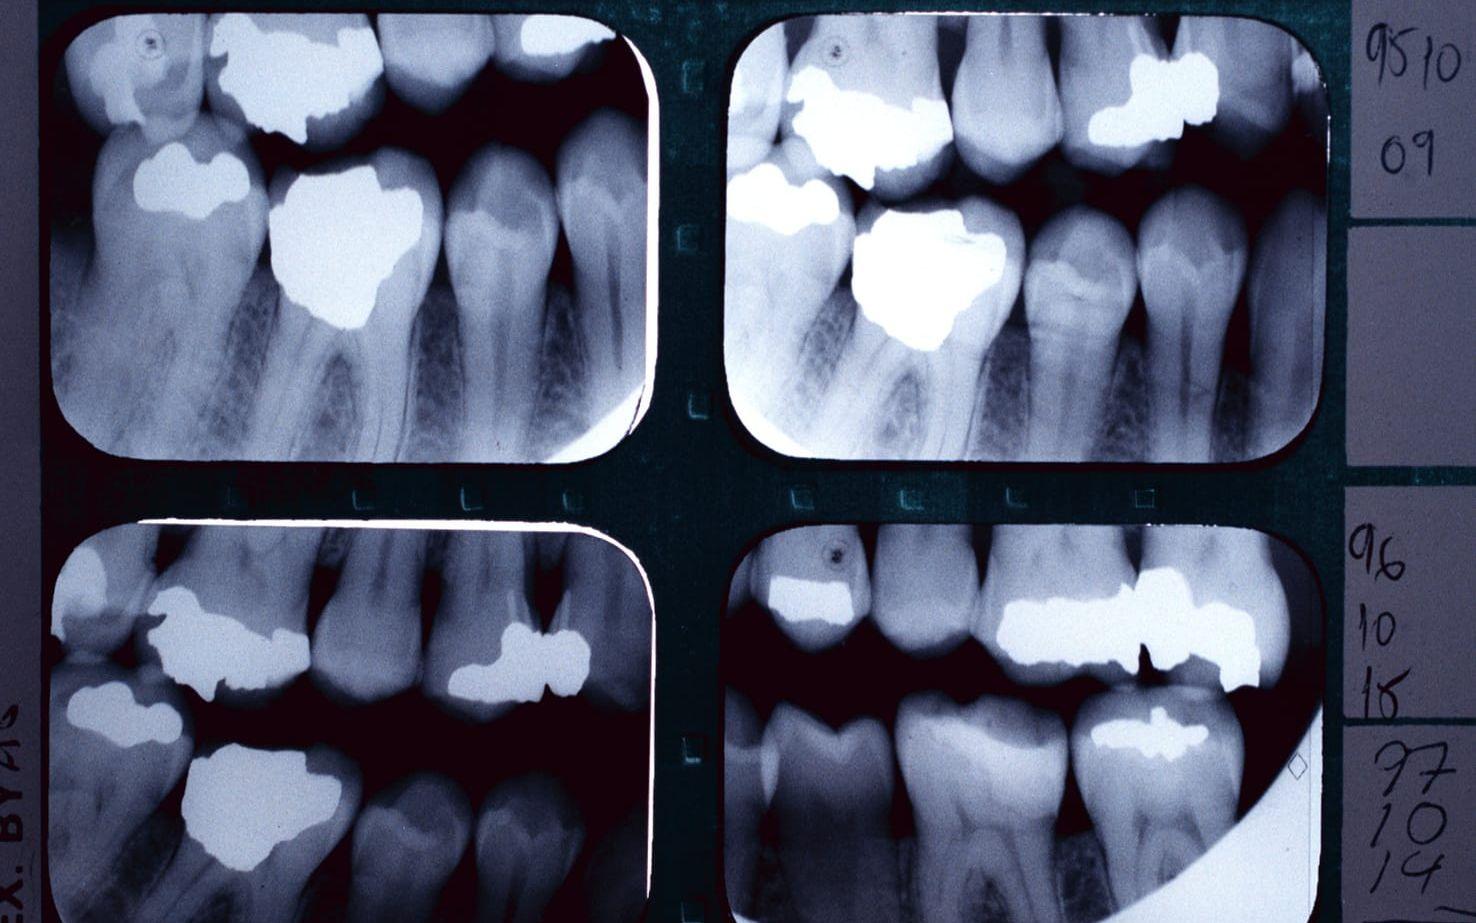

Oavsett förbudet och vad riksdag och regeringar har sagt har Socialstyrelsen och regionerna tydligt markerat, att de inte insett allvaret i att vi i Sverige under årtionden var det amalgamtätaste landet, på grund av skoltandvård, mödratandvård och olika tandvårdsreformer. Vid en kontroll av hur många gram kvicksilver det finns i enskildas tänder är det betydande mängder. Av dem som fick alla sina fyllningar under skoltiden har många amalgamet kvar tillsammans med andra konstruktioner som ökar avgången av kvicksilver. Trots förbudet, är det problem då människor behandlas för de olika symptom som kan ha direkt eller indirekt koppling till kvicksilvret och andra giftiga ämnen. Det har bevisats att kvicksilver förs över till foster via navelsträngsblod och förekommer i bröstmjölk, utöver att giftet ansamlas i organ som njurar, lever, hjärta, hjärna för att ta några exempel.